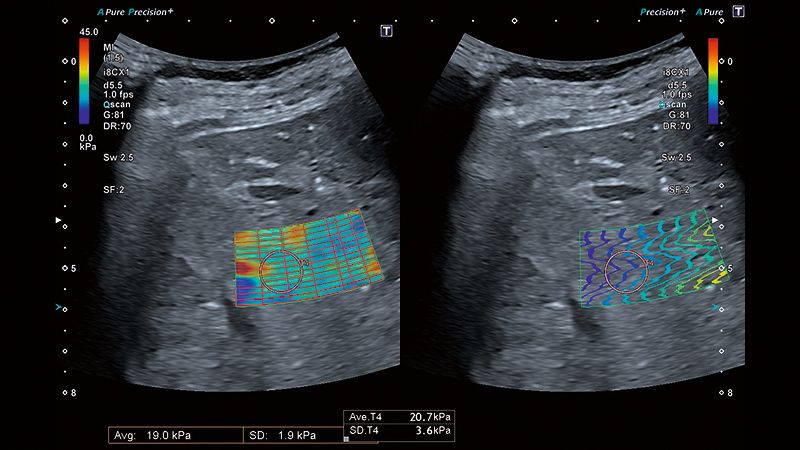

Залежно від ступеня фіброзу, паренхіма печінки демонструє підвищену віскоelasticity (в’язкопружність). Клініцисти досліджують жорсткість печінки як один із показників для діагностики фіброзу або цирозу печінки. Жорсткість печінки можна виміряти за допомогою еластографії зсувної хвилі (SWE).

Розумні карти допомагають візуалізувати поширення зсувної хвилі в режимі реального часу. Унікальна карта поширення від Canon – це потужний та інтуїтивно зрозумілий інструмент для візуальної оцінки якості еластограми.

Унікальний режим чотирьохканального перегляду Canon дозволяє одночасно порівняти швидкість, еластичність, поширення та дисперсію зсувної хвилі для більш повної та надійної оцінки стану печінки.